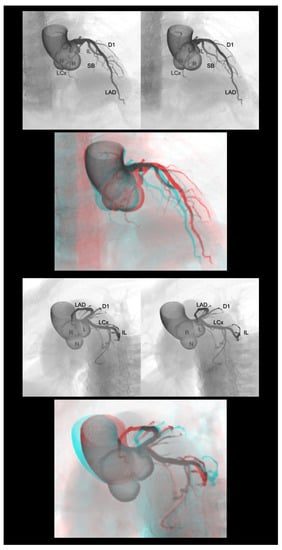

4.2. Coronary Arteries

4.3. Coronary Veins